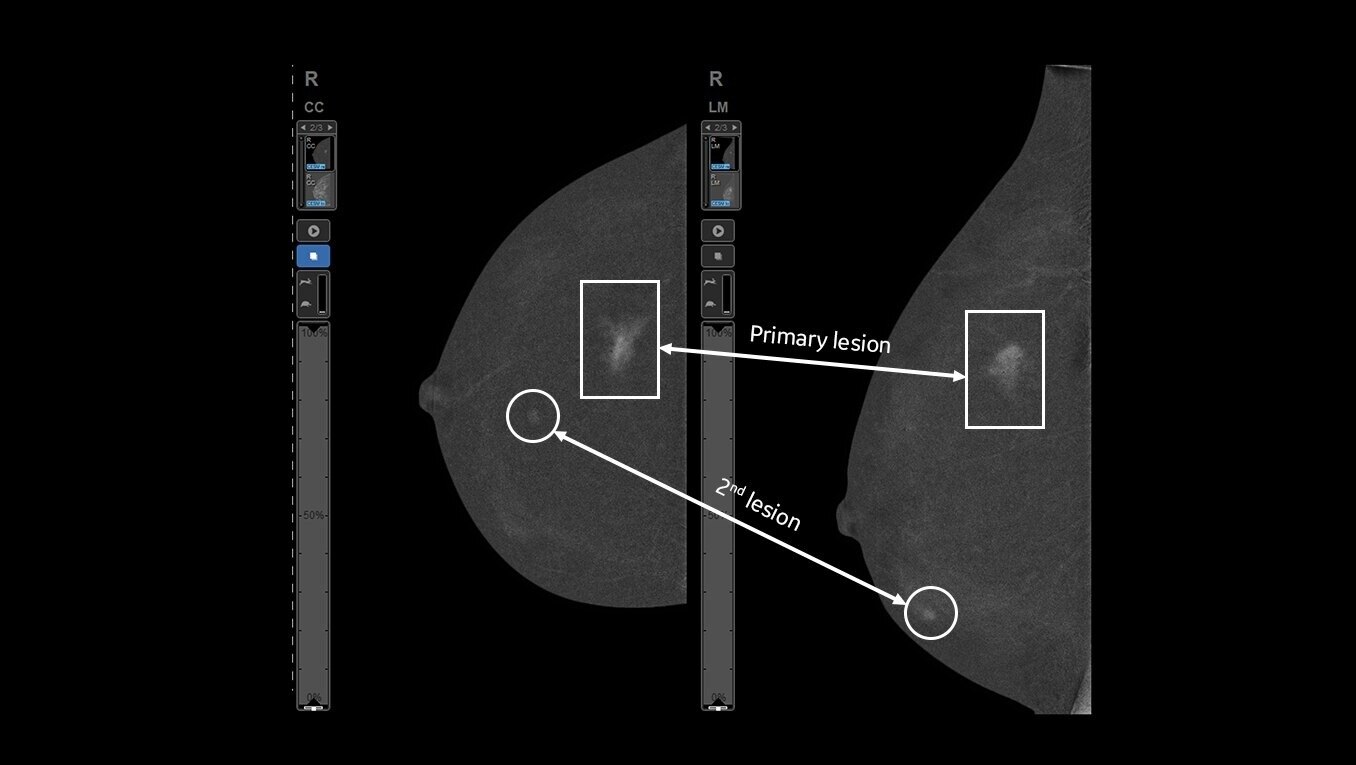

Clarity with complementary imaging

Compare like to like for increased biopsy correlation

With high sensitivity and specificity, CEM helps drive accuracy in biopsy. It allows you to clearly target suspicious areas by correlating lesion locations already identified in your patient’s diagnostic enhanced mammogram.